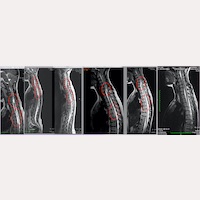

Fig.1 – Ressonâncias magnéticas de uma paciente e a sua evolução após o tratamento, mediante o Filum System®,

desde a primeira ressonância magnética pré-operatória até as de acompanhamento pós-operatório, 7 anos depois, nas quais se nota que os cistos medulares desapareceram.

“Efetivamente”, opina o Dr. M. Fiallos, especialista da equipe, “não só se detém a evolução da Siringomielia, evitando que os cistos captem mais tecido medular e que a necrose do mesmo se expanda, tal como se vê a curto prazo nas ressonâncias magnéticas pós-operatórias dos nossos pacientes, mas, inclusive, há casos nos quais, a médio e a longo prazo, as cavidades são reabsorvidas e vão desaparecendo nas imagens das ressonâncias magnéticas, sem o surgimento de novas cavidades (Fig.1). Às vezes, sequer deixam rastros desta patologia nos exames complementares e, paralelamente, é possível observar a melhoria clínica do paciente.”

Graças ao tratamento que aplicamos no nosso centro, que permite restabelecer a correta circulação no sistema nervoso central, “ os resultados conseguidos até o momento não são vistos imediatamente, porque são fruto de uma ação cirúrgica indireta, mas são muito satisfatórios – tanto objetivamente para os neurocirurgiães, como, subjetivamente, para os pacientes. Realizamos acompanhamentos pós-operatórios, aproximadamente ao longo de 7-10 anos, e comprovamos a diminuição das cavidades e a recuperação clínica dos pacientes”, afirma o neurocirurgião.